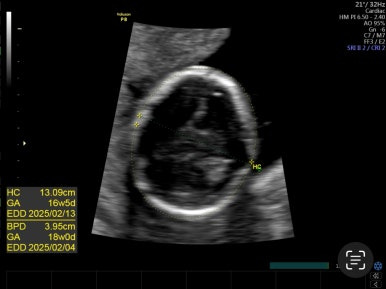

16주 2일

일반검진으로 이제 초음파로 아기를 한 눈에 들어오기 타이트해진 시기이다. 그 만큼 아기가 큰 걸 보면 신기하다.

그리고 성별을 알 수 있는 시기이다!